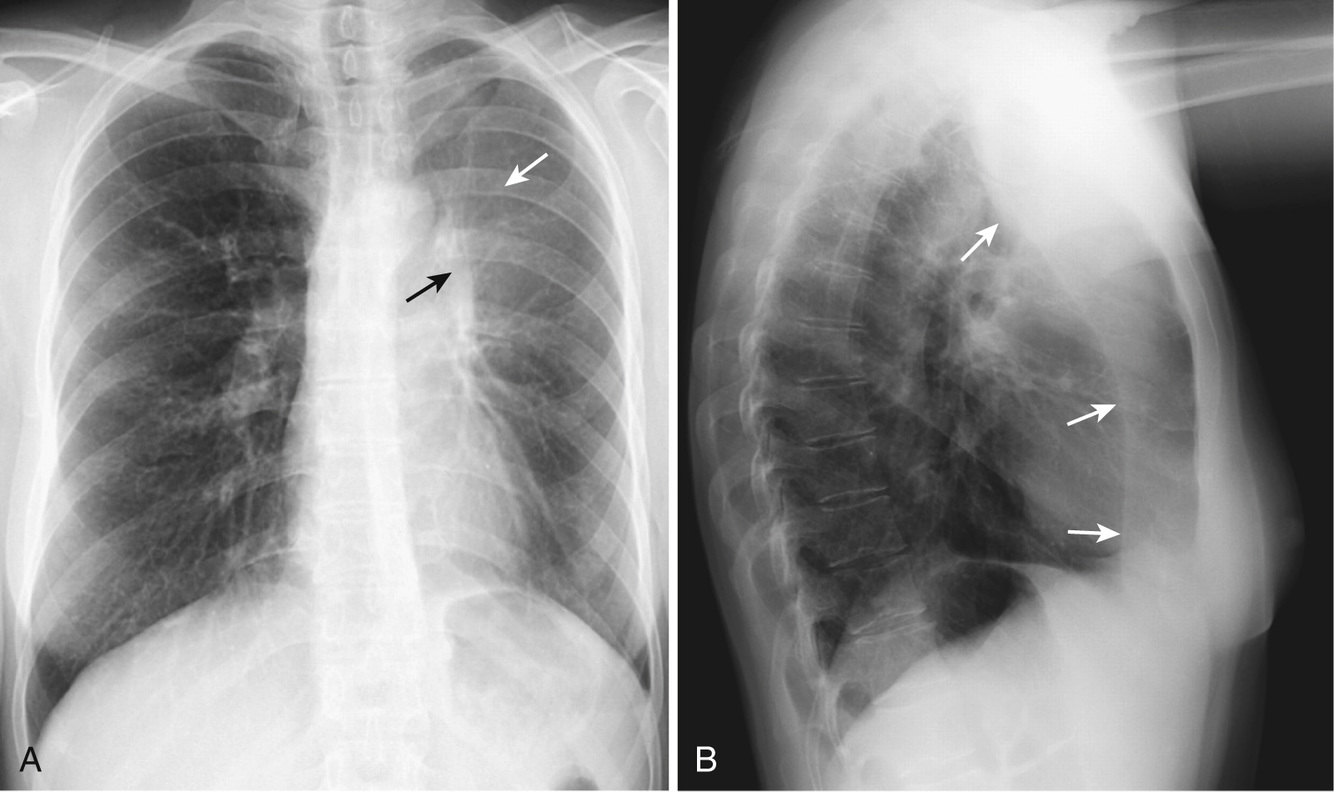

What is going on in this radiograph?

Left upper lobe obstructive atelectasis, aka Aunt Minnie sign again

Note the broad based triangle with an apex at the hilum and the movement of the major fissure towards the space of the collapse upper lobe.